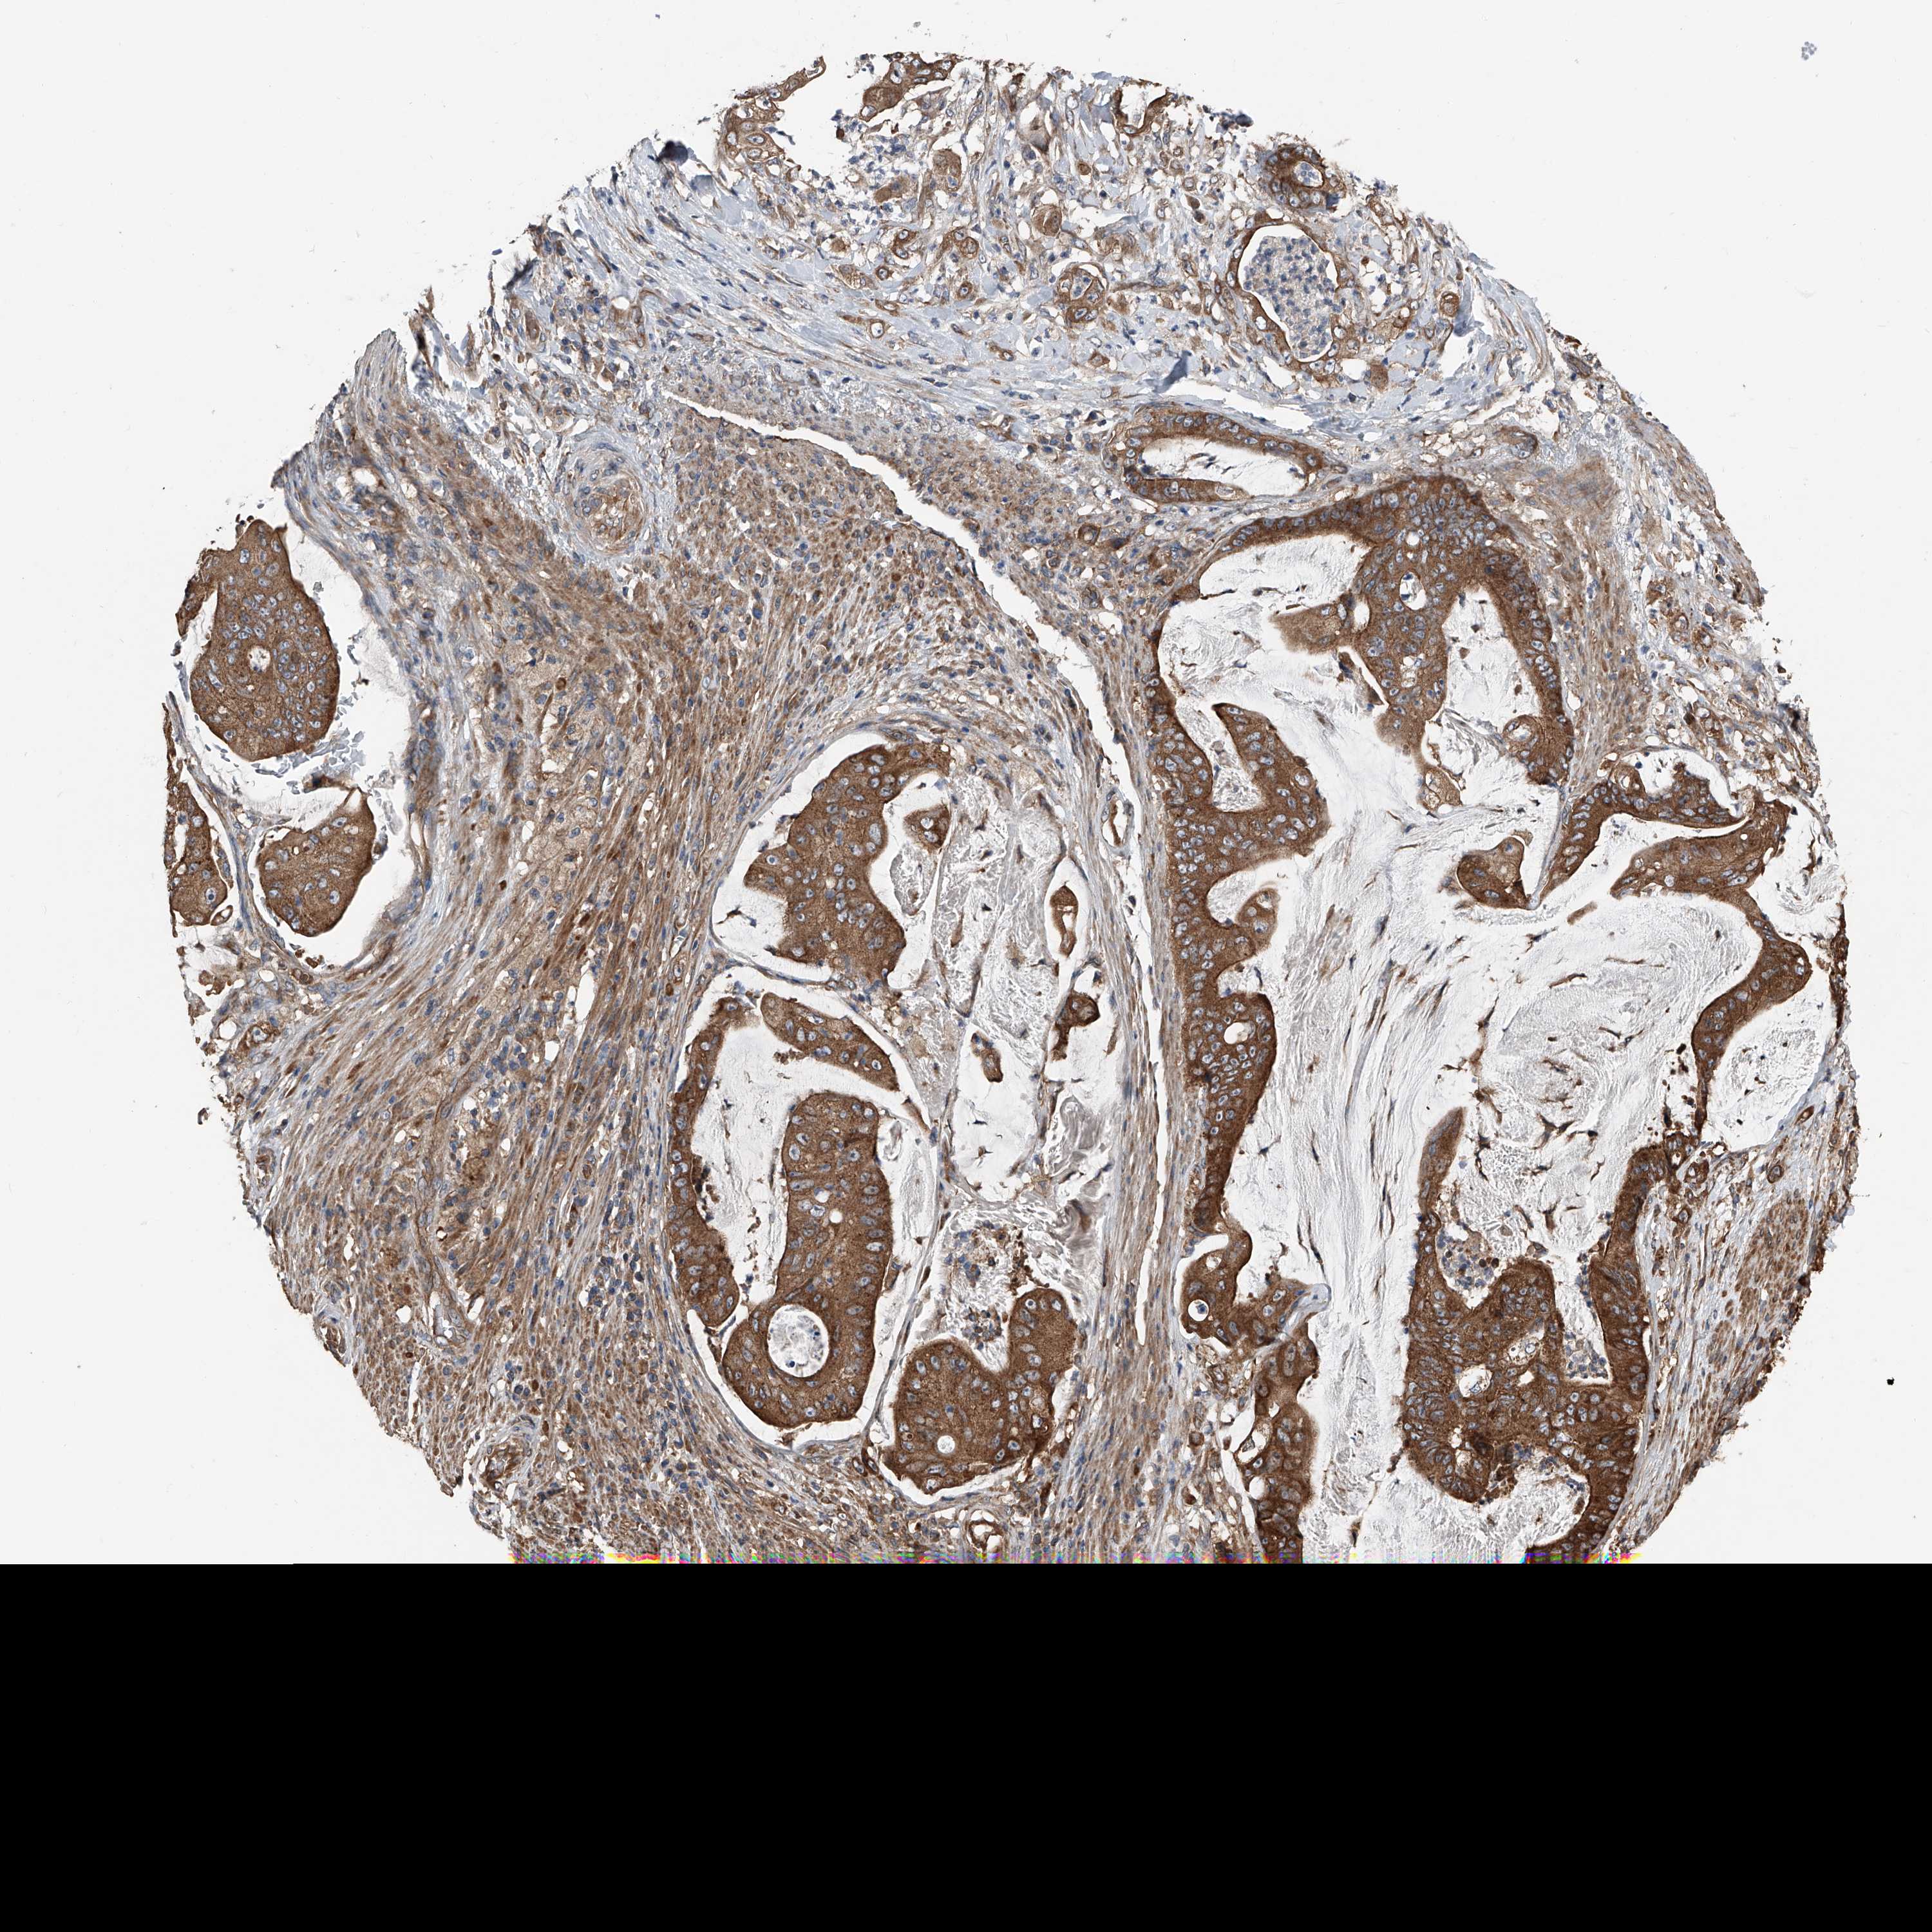

STOMACH CANCER - Protein expressioni

A mouse-over function shows sample information and annotation data. Click on an image to view it in a full screen mode. Samples can be filtered based on level of antibody staining by selecting one or several of the following categories: high, medium, low and not detected. The assay and annotation is described here.

Note that samples used for immunohistochemistry by the Human Protein Atlas do not correspond to samples in the TCGA dataset.

Antibody stainingi

Antibody staining in the annotated cell types in the current human tissue is reported as not detected, low, medium, or high, based on conventional immunohistochemistry profiling in selected tissues. This score is based on the combination of the staining intensity and fraction of stained cells.

Each image is clickable and will lead to virtual microscopy that enables deeper exploration of all samples and also displays staining intensity scores, fraction scores and subcellular localization as well as patient and tissue information for each sample.

Antibody HPA029109

Staining

High

Medium

Low

Not detected

Intensity

Strong

Moderate

Weak

Negative

Quantity

>75%

75%-25%

<25%

None

Location

Nuclear

Cytoplasmic/membranous

Cytoplasmic/membranous,nuclear

Adenocarcinoma, NOS